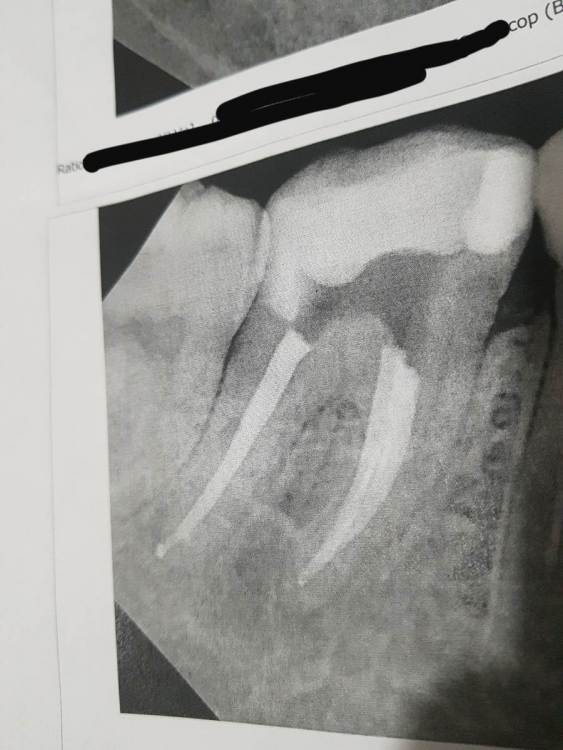

Анастасия577 Опубликовано 23 декабря, 2024 Поделиться Опубликовано 23 декабря, 2024 22 часа назад, Бардо сказал: Проблемы есть с обоими зубами, возможно имеет смысл съездить в ближайший более-менее крупный город, в наше время уже нет большой проблемы найти доктора, который может справиться с такими зубами. Вам как пациенту, повторюсь, стоит обращать внимание на наличие увеличения и изоляции. Сделала более точные снимки, врач сказал, что всё нормально там. Вы что скажете? Ссылка на комментарий

Бардо Опубликовано 21 декабря, 2024 Поделиться Опубликовано 21 декабря, 2024 2 часа назад, Анастасия577 сказал: Скажите пожалуйста, а вот это уже слишком сильно вышло за пределы? Или это норма и тоже рассосётся со временем? Не думаю, что это рассосется, но мы боремся не с пломбировочным материалом за зубом, а с инфекцией в зубе. В вашем зубе скорее всего есть еще корневые каналы, я бы посоветовал вам обратиться к доктору, который работает с увеличением и изоляцией. 1 Ссылка на комментарий

Бардо Опубликовано 22 декабря, 2024 Поделиться Опубликовано 22 декабря, 2024 45 минут назад, Анастасия577 сказал: Какой из них? Там два разных зуба. В нашей местности нет таких специалистов. Я перепроверила у другого врача, в другой клинике, в другом городе, он сказал что для наших городов это одна из лучших работ, в основном каналы чистят хуже. Проблемы есть с обоими зубами, возможно имеет смысл съездить в ближайший более-менее крупный город, в наше время уже нет большой проблемы найти доктора, который может справиться с такими зубами. Вам как пациенту, повторюсь, стоит обращать внимание на наличие увеличения и изоляции. Ссылка на комментарий